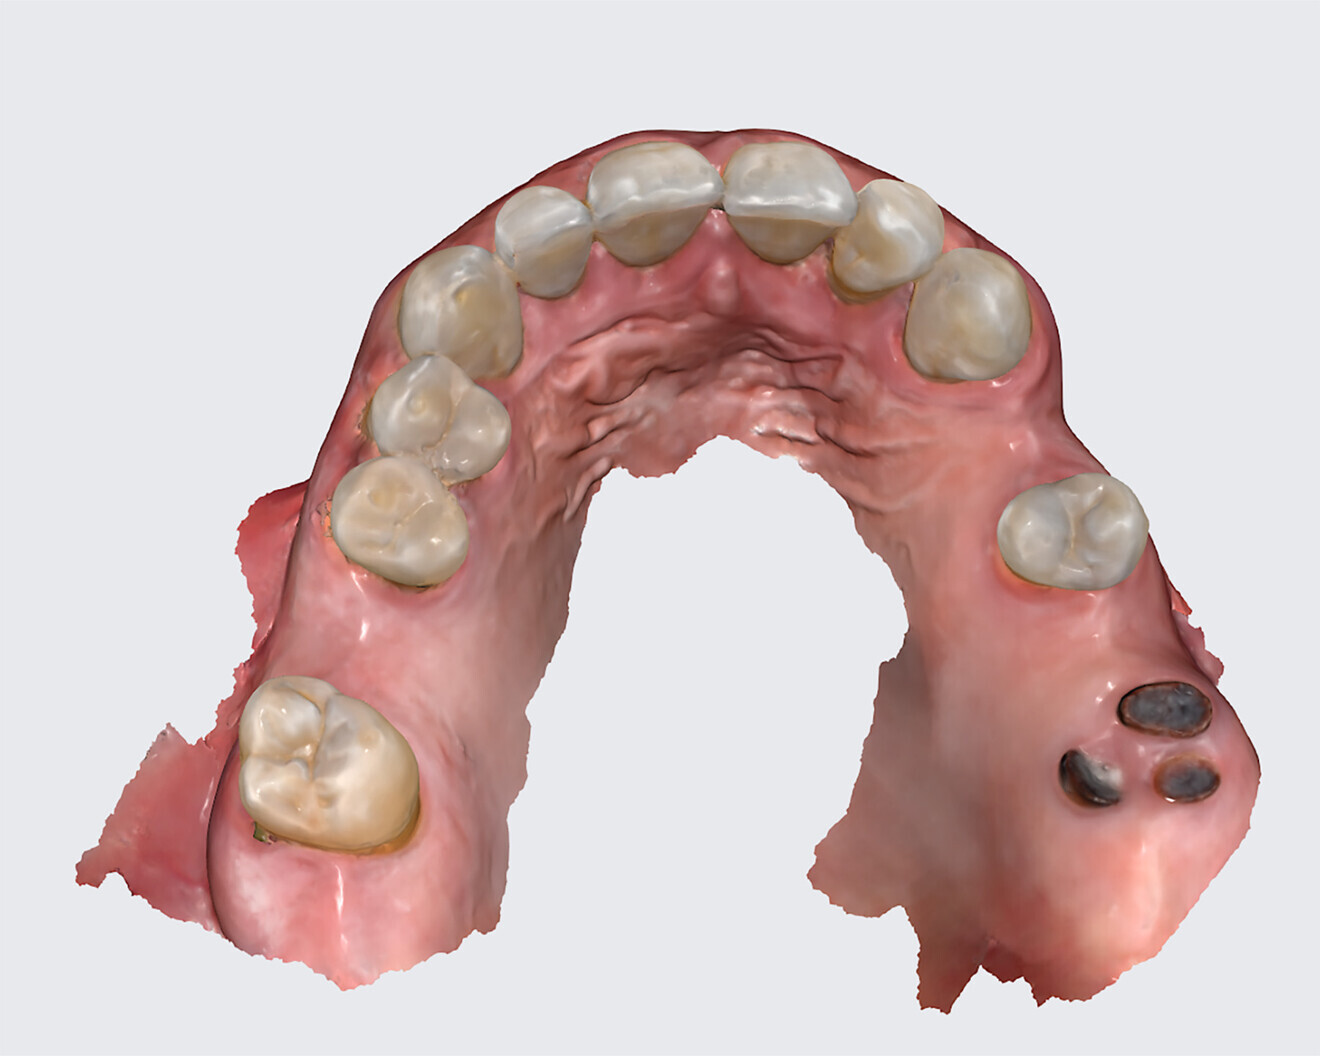

The following case exhibits the features and benefits of utilising Grammetry in combination with innovative screw technology. The 63-year-old male patient with a non-contributory medical history presented with failing dentition in both arches. Diagnostic records were collected, including full-mouth digital radiographs (RVG 6200, Carestream Dental; Fig. 11a), intra-oral scans (Medit i700 wireless; Figs. 11b & c), a large field of view CBCT scan (Carestream 9600; Fig. 11d), and intra-oral and extra-oral photographs (Fig. 11e). The mandible contained an impacted canine as well as several mobile and painful teeth. The maxilla was in a similar condition, having deteriorating, painfully mobile teeth, as well as extensive caries. While the bone loss was significant in the mandible, the vertical dimension of occlusion (VDO) allowed for both arches to be treated with an FP-1 prosthesis.

Fig. 11b: Maxillary intra-oral scan.